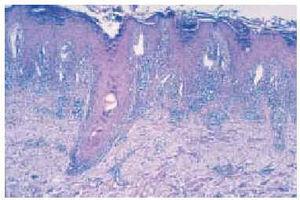

Fig. 3.--Quiste de tipo millium rodeado de infiltrado inflamatorio crónico adherido a la vaina epitelial externa en placa retroauricular izquierda. (Hematoxilina-eosina, x80.)

La imagen histológica del LPFTR es la de un liquen plano pilaris caracterizado por la presencia en la dermis de numerosos folículos pilosos, a veces dilatados y quísticos, y quistes foliculares llenos de láminas de queratina ortoqueratósica. Estas formaciones están rodeadas de un infiltrado inflamatorio, habitualmente linfocitario denso o linfohistiocitario a veces con plasmocitos y eosinófilos, que se encuentra pegado a la vaina epitelial externa de los folículos pilosos y a la pared de los quistes foliculares con exocitosis y, ocasionalmente, formación de hendiduras. El infiltrado celular dérmico puede igualmente alcanzar la epidermis, tomando una disposición en banda. Raramente se encuentran el pigmento melánico y cuerpos de Civatte. La epidermis de superficie puede ser normal, adelgazada o, con más frecuencia, hiperplásica. La capa córnea presenta una hiperqueratosis ortoqueratósica que forma tapones córneos que contienen raramente focos de paraqueratosis. La capa granulosa suele ser frecuentemente hiperplásica así como el cuerpo mucoso. Puede encontrarse una vacuolización de la capa basal1-8.